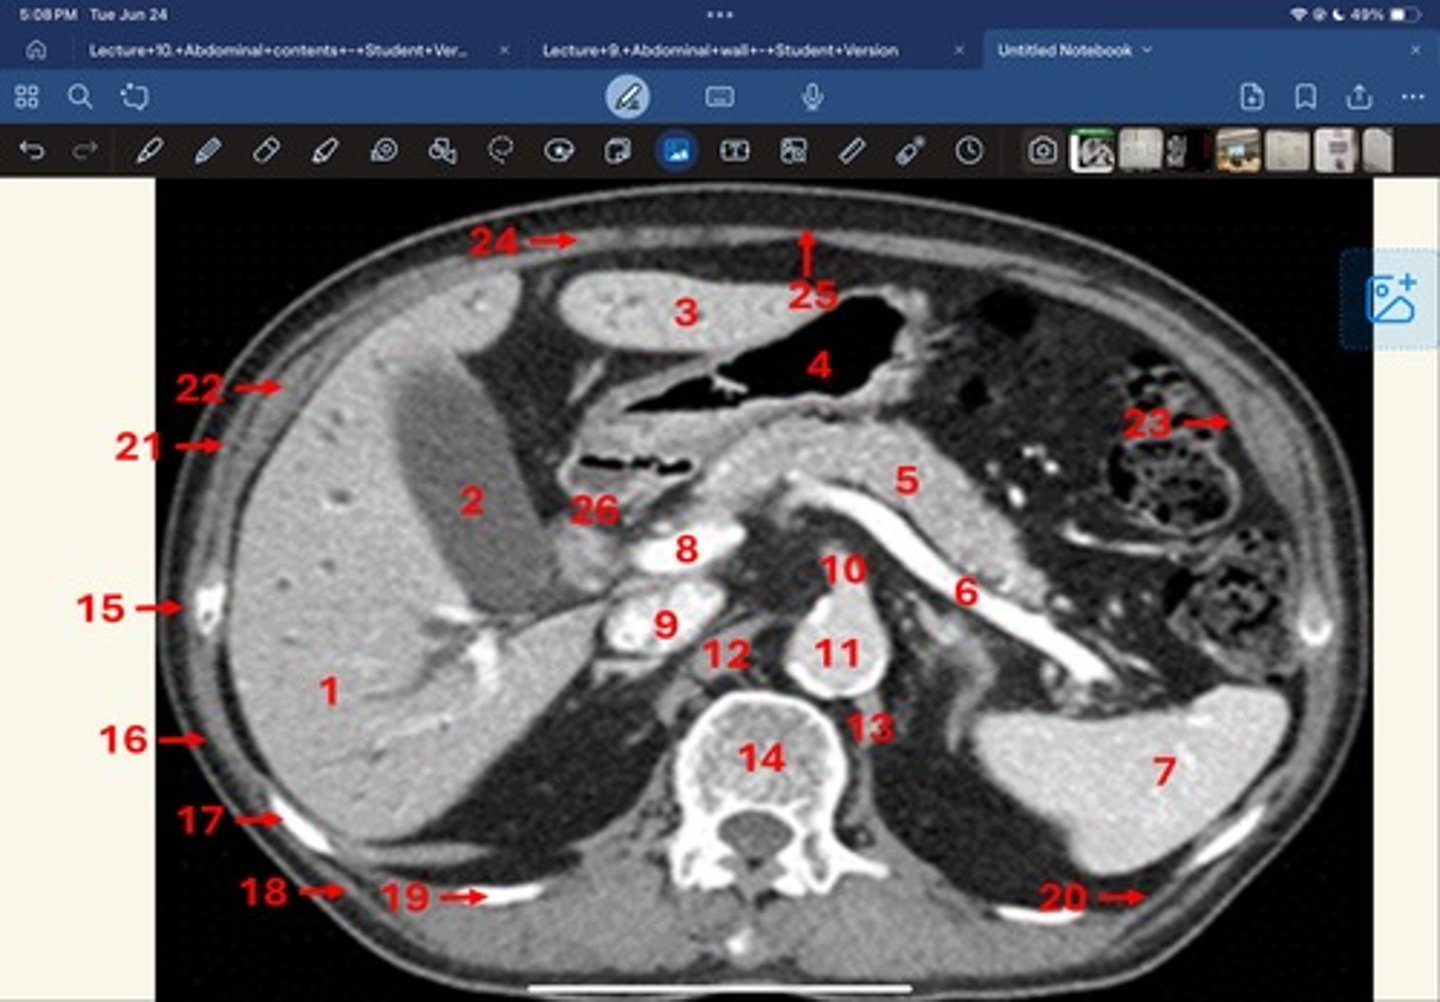

Right lobe of liver

What is 1

Gallbladder

What is 2

Left lobe of liver

What is 3

Stomach, pylorus

What is 4

Pancreas

What's 5

Splenic vein

What's 6

Spleen

What's 7

superior mesenteric vein

What's 8

Inferior vena cava

What's 9